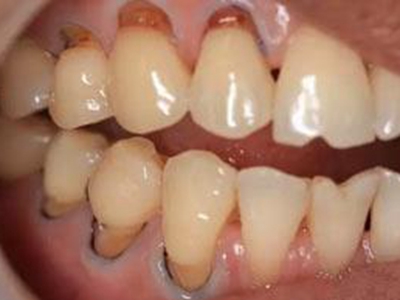

牙齿

缺损

酸蚀症牙齿缺损不平整图

酸蚀症患者的牙齿会发生缺损,轻度时仅表现为牙齿尖端凹凸不平,有少量骨质缺失,缺损处有黄褐色至红褐色斑点,该病可能是长期接触外源性酸性物质而致病。